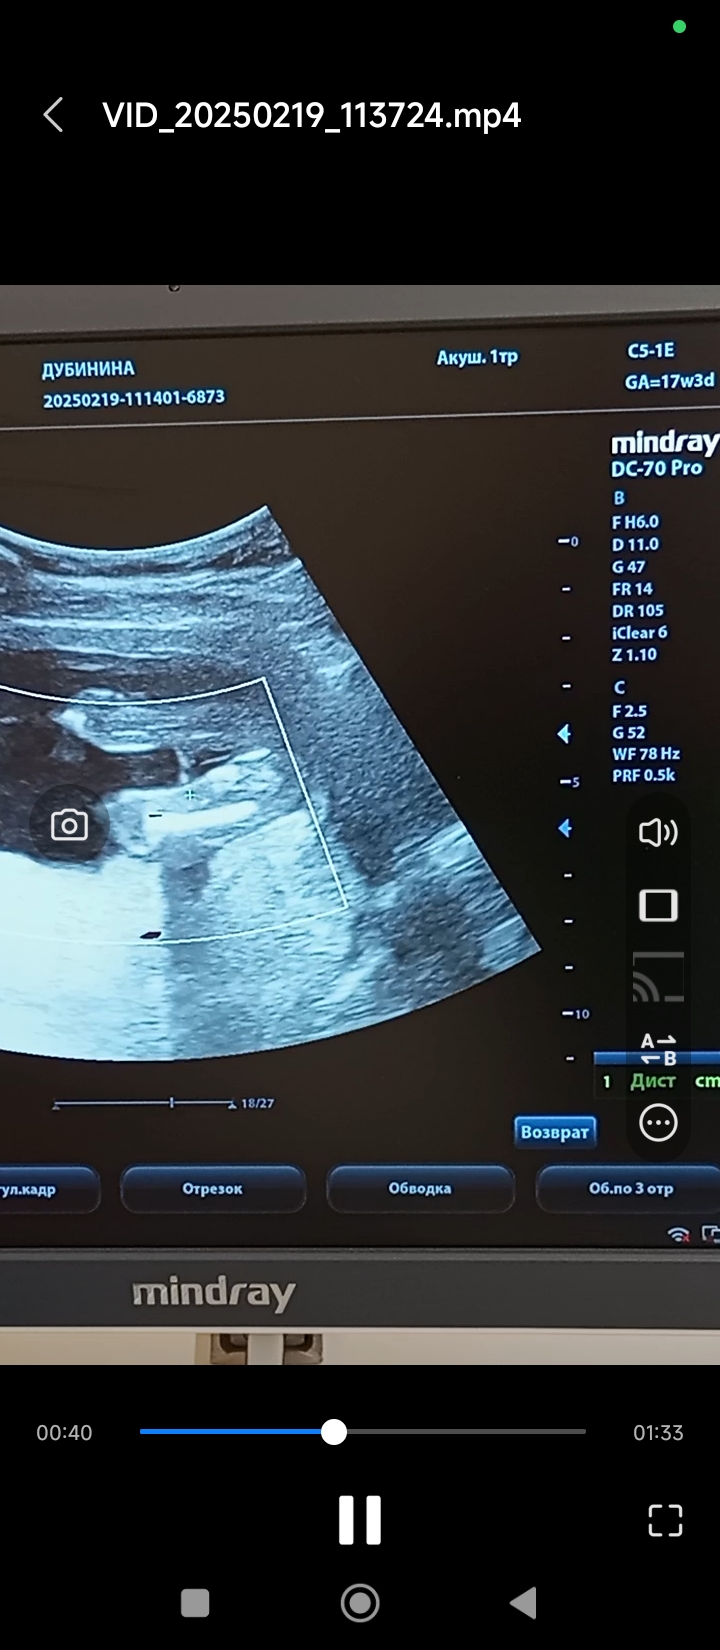

Валентина в Благополучная беременность 9 месяцев Пол мальчик или девочка? Пол малыша Девочки а здесь кого видно?)) Посмотрите еще 20 записей на эту тему Отменить Ответить Eva Девочка тут 01.03.2025 Ответить Яна Парнем чет не пахнет тут😂 27.02.2025 Ответить Татьяна Похоже на девочку 27.02.2025 Ответить Мама Лиля Девчуля 27.02.2025 Ответить Мила Девочка 27.02.2025 Ответить Людмилка Девочка🤗 27.02.2025 Ответить Camy Девочка 27.02.2025 Ответить Natalie ))))) Camy, согласна 27.02.2025 Ответить Пол 2 скрининг 20 нед Чаты Беременных Выберите чат: Январята-2026 Февралята-2026 Мартята-2026 Апрелята-2026 Майчата-2026 Июнята-2026 Июлята-2026 Августята-2026